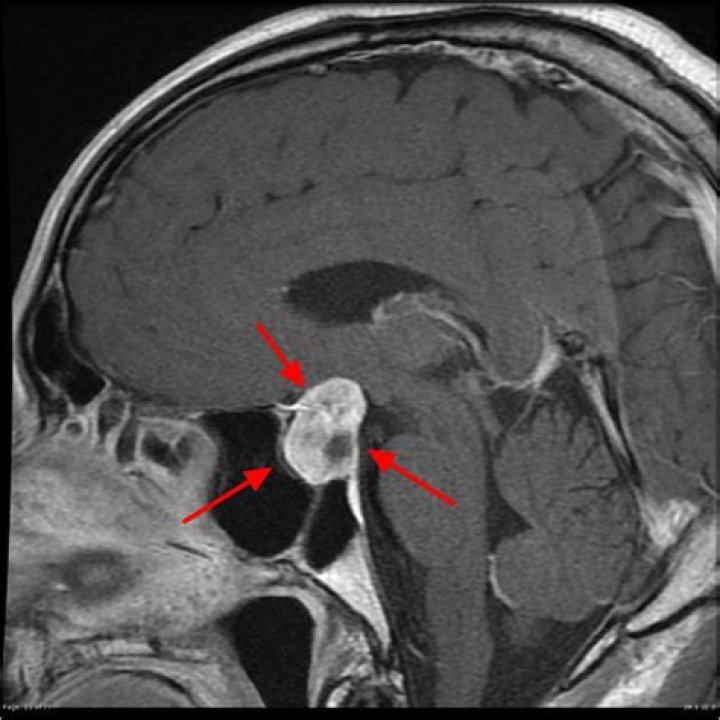

. These benign tumors do not spread outside the skull. They usually stay in the sella turcica (the tiny space in the skull that the pituitary gland sits in). Sometimes they grow into the boney walls of the sella turcica and nearby tissues, like blood vessels, nerves, and sinuses.

When pituitary tumors grow they can compress the above-mentioned structures and cause symptoms. Figure 1. A cross-section of the pituitary gland (green) shows its relationship to the optic chiasm, the sphenoid sinus, and the cavernous sinuses on each side.